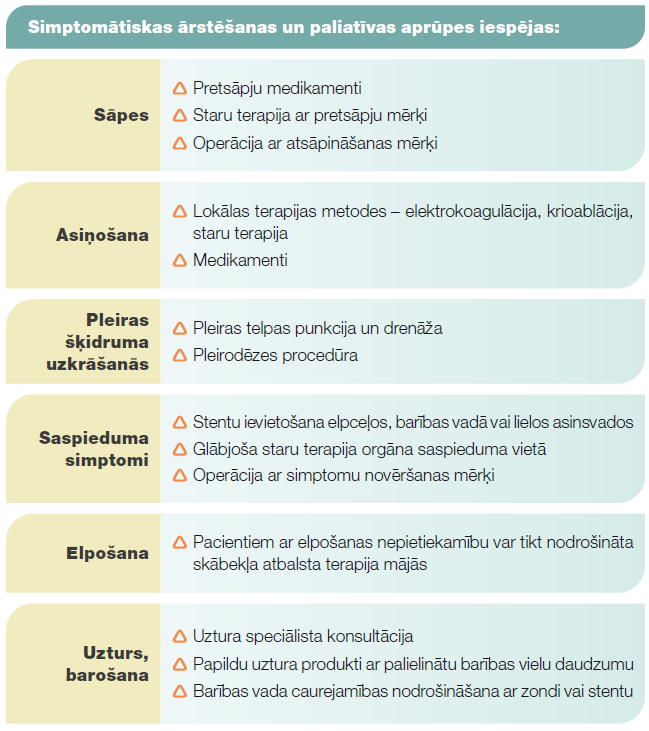

Simptomātiska terapija un paliatīva aprūpe

Tā ir nespecifiska plaušu vēža ārstēšana. Simptomātiskas terapijas un paliatīvas aprūpes mērķis ir uzlabot pacienta dzīves kvalitāti, atvieglot vai novērst plaušu vēža radītus simptomus. Simptomātiska terapija var tikt nodrošināta vienlaicīgi ar specifisku plaušu vēža ārstēšanu - staru terapiju, medikamentozu terapiju, operāciju, vai arī pēc tās pabeigšanas. Atsevišķos gadījumos specifiska plaušu vēža terapija nav iespējama pacienta vispārēji apgrūtināta stāvokļa dēļ, terapija priekš pacienta var būt pārāk smaga vai arī pacients no specifiskās ārstēšanas atsakās. Simptomātisku terapiju un paliatīvu aprūpi nodrošina ģimenes ārsts un paliatīvās aprūpes speciālists. Nepieciešamības gadījumā ārstēšanai tiek piesaistīti speciālisti, kas var veikt manipulācijas simptomu atvieglošanai. Enterāla un parenterāla uztura nodrošināšana ir nepieciešama pacientiem ar nepietiekamu barojumu. Par uzturu pacients var saņemt ārsta dietologa konsultāciju uztura kabinetā, ārstējošais ārsts var rekomendēt papildu uztura produktus. Elpceļu caurejamības nodrošināšanai un asiņošanas kontrolei var izmantot lokālās terapijas metodes: elektrokoagulāciju, krioablāciju, elpceļu caurlaidības atjaunošanu ar stentu. Šīs procedūras veic torakālais ķirurgs. Dažiem pacientiem var būt nepieciešama skābekļa atbalsta terapija, ko ar skābekļa koncentrātora palīdzību var nodrošināt mājas apstākļos. Pacientiem ar izplatītu plaušu vēzi starp pleiras lapiņām var uzkrāties šķidrums. Tas var apgrūtināt elpošanu. Lai to atrisinātu, veic pleiras telpas punkciju un šķidruma drenāžu. Ja šķidrums krājas atkārtoti, ir iespēja veikt procedūru, kuras laikā pleiras lapiņas salipina savā starpā ar speciālo talka pulveri - talka pleirodēzi. Rezultātā starp pleiras lapiņām šķidrums neuzkrājas. Ja plaušu vēzis vai vēža skartie limfmezgli cauraug barības vada sieniņu, var būt apgrūtināta rīšana. Barības vada caurejamību var atjaunot ar stenta ievietošanu. Slimības radītu sāpju gadījumā atbilstoši sāpju intensitātei un raksturam nozīmē pretsāpju medikamentus. Piemērotākas pretsāpju terapijas izvēlei atsevišķos gadījumos var pieaicināt algologu, sāpju speciālistu. Ja zināms sāpju avots, piemēram, kaulu metastāzes, vai arī plaušu audzējs ieaug krūškurvja sienā, tad sāpju atvieglošanai var izmantot staru terapiju.